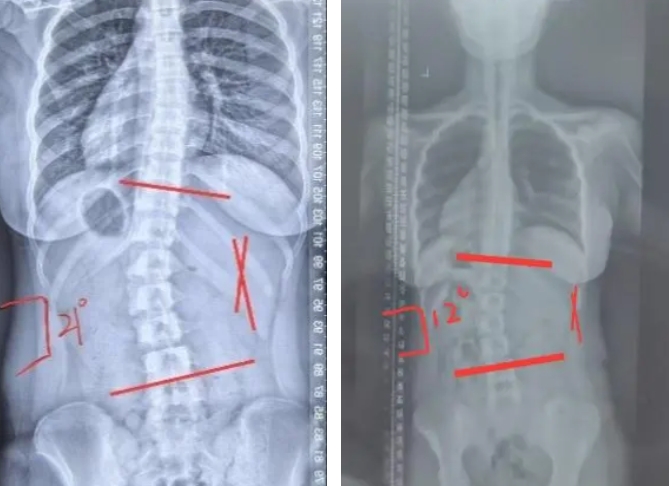

13岁的小彤体检时发现体态不佳,进行拍片检查后,到集团针推康复中心就诊。经过系统评估和专业测量,发现小彤脊柱侧弯Cobb角度达到21°,同时伴有颈椎反弓、高低肩等情况。这意味着,她的治疗和恢复注定是一场漫长而艰辛的征程。

经过6个月的治疗后,小彤复查Cobb角度已降至12°,体态已基本恢复正常,疗效显著。专家团队还根据小彤的恢复情况,制定了详细的后续康复计划,重点加强姿势训练和核心肌群的锻炼,以巩固治疗效果并预防复发。